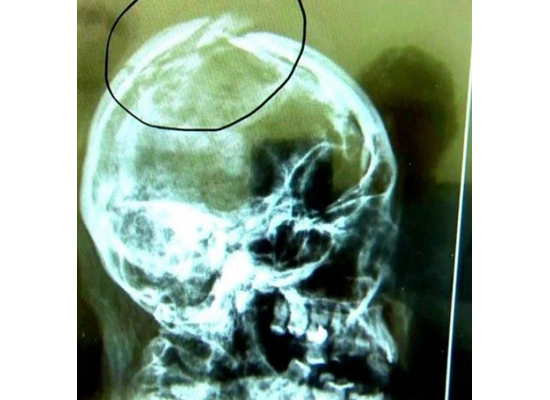

وعثرت الشرطة على جثة الزوجة 'مارسيا ميراندا' على مسافة مترين تقريبا تحت فناء تم بناؤه حديثا في منزل مستأجر بالقرب من ساو باولو بالبرازيل بعد انفصالها عن شريكها- ابن الزوجين – وأب طفليها.

وكانت الجثة متحللة بشدة لدى العثور عليها، ولم يكن من السهل تحديد الهوية سوى من خلال بصمات الأصابع، وتعتقد الشرطة أنه دفنت على قيد الحياة، ولكن ينتظر فحص الطب الشرعي.